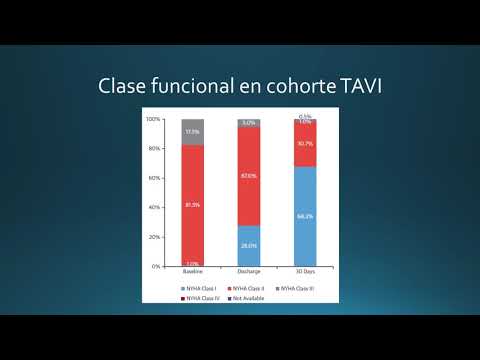

TAVI en pacientes con EAo severa sintomática de bajo riesgo. Dra. Ana Laura Mori. Residencia de Cardiología. Hospital C. Argerich. Buenos Aires